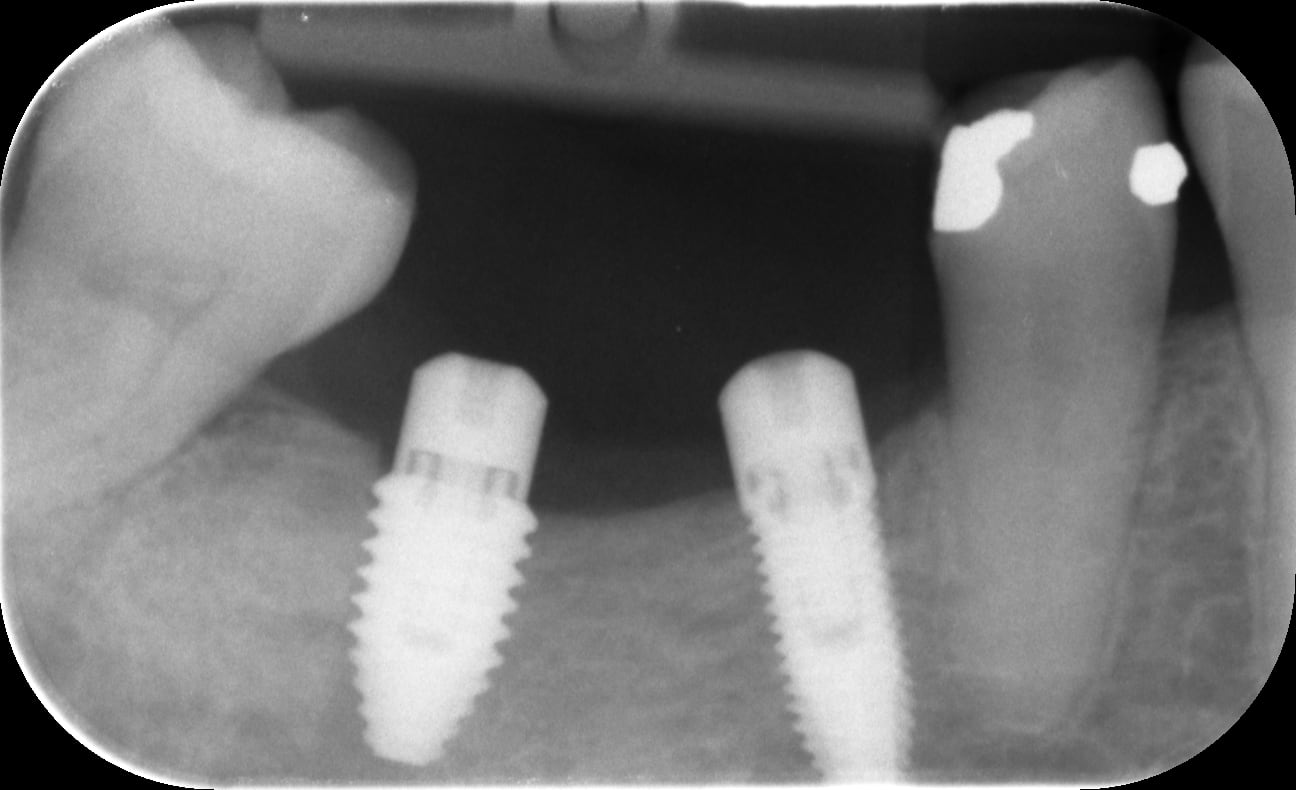

j'ai placé ces deux implants le mois dernier

niveau 46 47

l'os est de type d4

au niveau de 47, la pose de l’implant a été réalisée entièrement à la clé dynamo et 40 Ncm en final bien bloqué

un mois plus tard pour un contrôle je constate une inflammation de la gencive autour de 47 et une vis mobile

dépose de l'implant qui semble égressé à la radio

Un type D4 à la mandibule c'est pas banal.

- Il y a sans doute un problème d'axe on voit déjà que les deux implants ne sont pas bien positionnés en mésio-distal, je mets une pièce sur un mauvais positionnement vestibulo-lingual aussi avec un os trop fin ou carrément une fenestration osseuse en lingual.

- L'implant distal est très conique, pas forcément adapté à l'os très corticalisé (en général) à la mandibule.